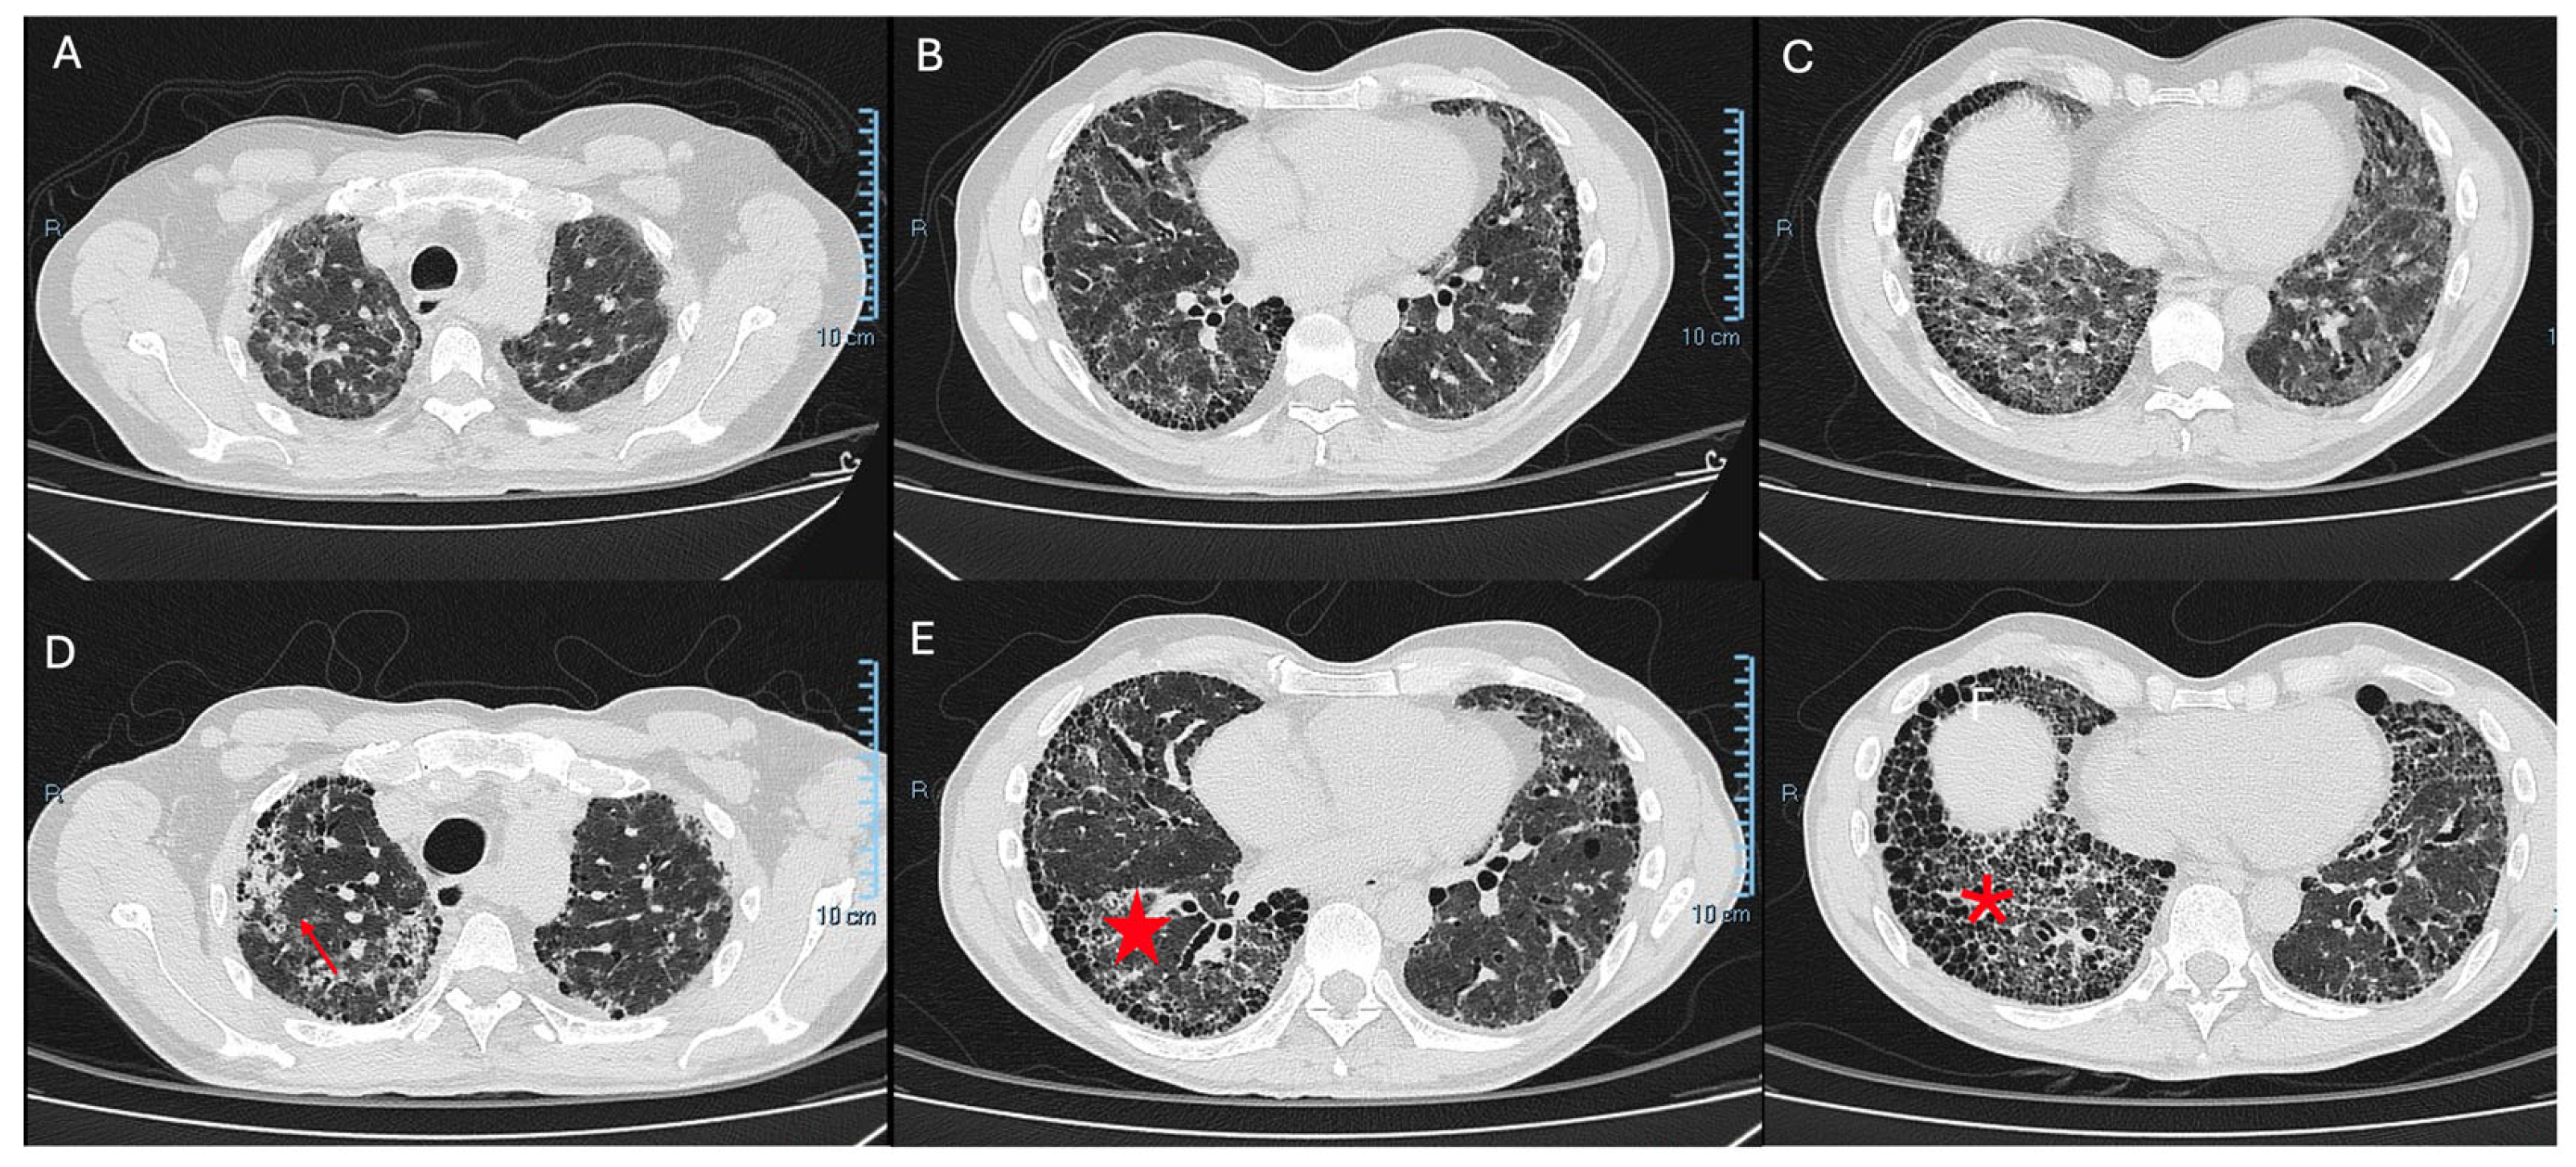

Current guidelines include radiographic progression as one of the diagnostic criteria for PPF, specifically the presence of one or more of the following radiological findings (Figure 1):

• Increased extent or severity of traction bronchiectasis and bronchiolectasis;

• New ground-glass opacity with traction bronchiectasis;

• New fine reticulation;

• Increased extent or increased coarseness of reticular abnormality;

• New or increased honeycombing;

• Increased lobar volume loss.

Figure 1. Definitive UIP fibrotic pattern (AC). Architectural distortion of the lung parenchyma with a heterogeneous temporal and spatial distribution, with subpleural reticulation, thickening of the interlobular septa, and apical–basal gradient. (D) Definitive UIP fibrotic pattern, with signs of progressive pulmonary fibrosis during one year of follow-up. (Red arrow) Increased extensive architectural distortion of the lung parenchyma, apex–basal gradient. (E) (Red star) Traction bronchiectasis–bronchiolectasis. (F) Volume loss and (red asterisk) exuberant honeycombing.

It is well established that pulmonary volume loss, the presence of a UIP pattern, traction bronchiectasis, and widespread fibrotic extension indicate a diffuse fibrosing process with a progressive course—independent of the underlying ILD diagnosis [14,15]. Therefore, a comprehensive radiological assessment is essential. However, this evaluation is significantly limited by inter-observer variability in objective quantification [4].